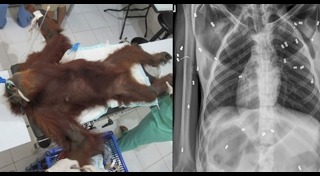

นายพรานใจร้าย เอาปืนยิงอุรังอุตังไร้ทางสู้ กระสุนฝัง 16 นัด ผ่าออกไม่ได้

แม่อุรังอุตัง ปกป้องลูกน้อยจนถูกนักล่ายิง 74 นัด สลด...สุดท้ายช่วยแม่ได้ แต่ลูกไม่รอด